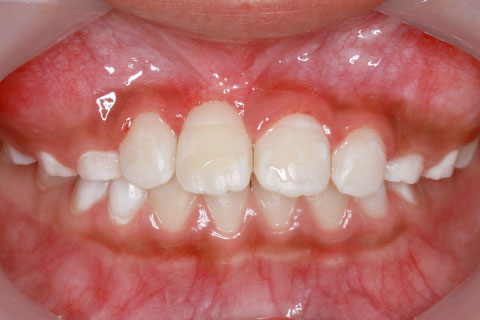

子供の乳歯が抜けて、かなりの時間が経つのに永久歯が生えてこないと心配して来院される親御様は多くいらっしゃいます。この場合、レントゲンにて確認すると大体の場合、もうしばらく待っていれば生えてくるであろうと予測がつきます。しかし、稀に歯の位置異常により、埋まったままの状態で生えてこないことがあります。この場合、待っていても生えてきませんので、矯正力により歯を引っ張り出す必要があります。これを矯正学では開窓・牽引術と呼び、歯肉を切開して、歯の表面を露出させ、そこに矯正器具を付けて、良好な位置まで引っ張り出すという治療法です。

開窓・牽引の症例